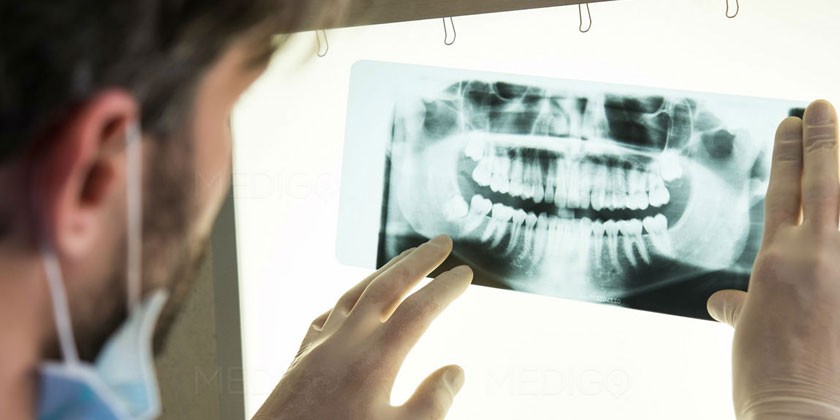

Диагностика гингивита

При наличии симптомов гингивита нужно обратиться к стоматологу или пародонтологу. Первым делом врач проводит опрос пациента, визуальный и инструментальный осмотр ротовой полости. Специалист обращает внимание на присутствие характерного налета и состояние десны вокруг зубов. Подтвердить гингивит помогают следующие функциональные тесты и методы диагностики:

- Пародонтограмма. Это исследование функционального состояния периодонта, десны, альвеолярных отростков – комплекса тканей, окружающих зуб и удерживающих его в альвеоле.

- Рентген. Необходим для проверки состояния костных тканей.

- Микробиологическое исследование. Проводится с целью исключения патологий со сходной симптоматикой: пародонтозом, пародонтитом.

Для диагностики гингивита важно обратиться к стоматологу, который проведет осмотр полости рта и, при необходимости, назначит рентгенографию. Лечение гингивита включает медикаментозные препараты, такие как антисептические растворы и противовоспалительные препараты. Кроме того, врачи рекомендуют использовать народные средства, такие как прополис, календулу и эфирные масла, для укрепления здоровья десен.